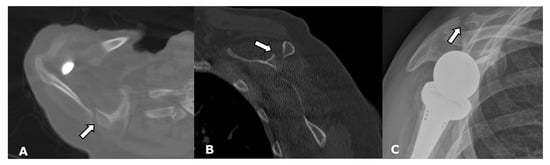

4.2.1. Loosening and Hardware Dissociation

4.2.2. Stress Shielding and Fractures

5.2. Reverse Arthroplasty

Reverse Total Shoulder Arthroplasty (RTSA)